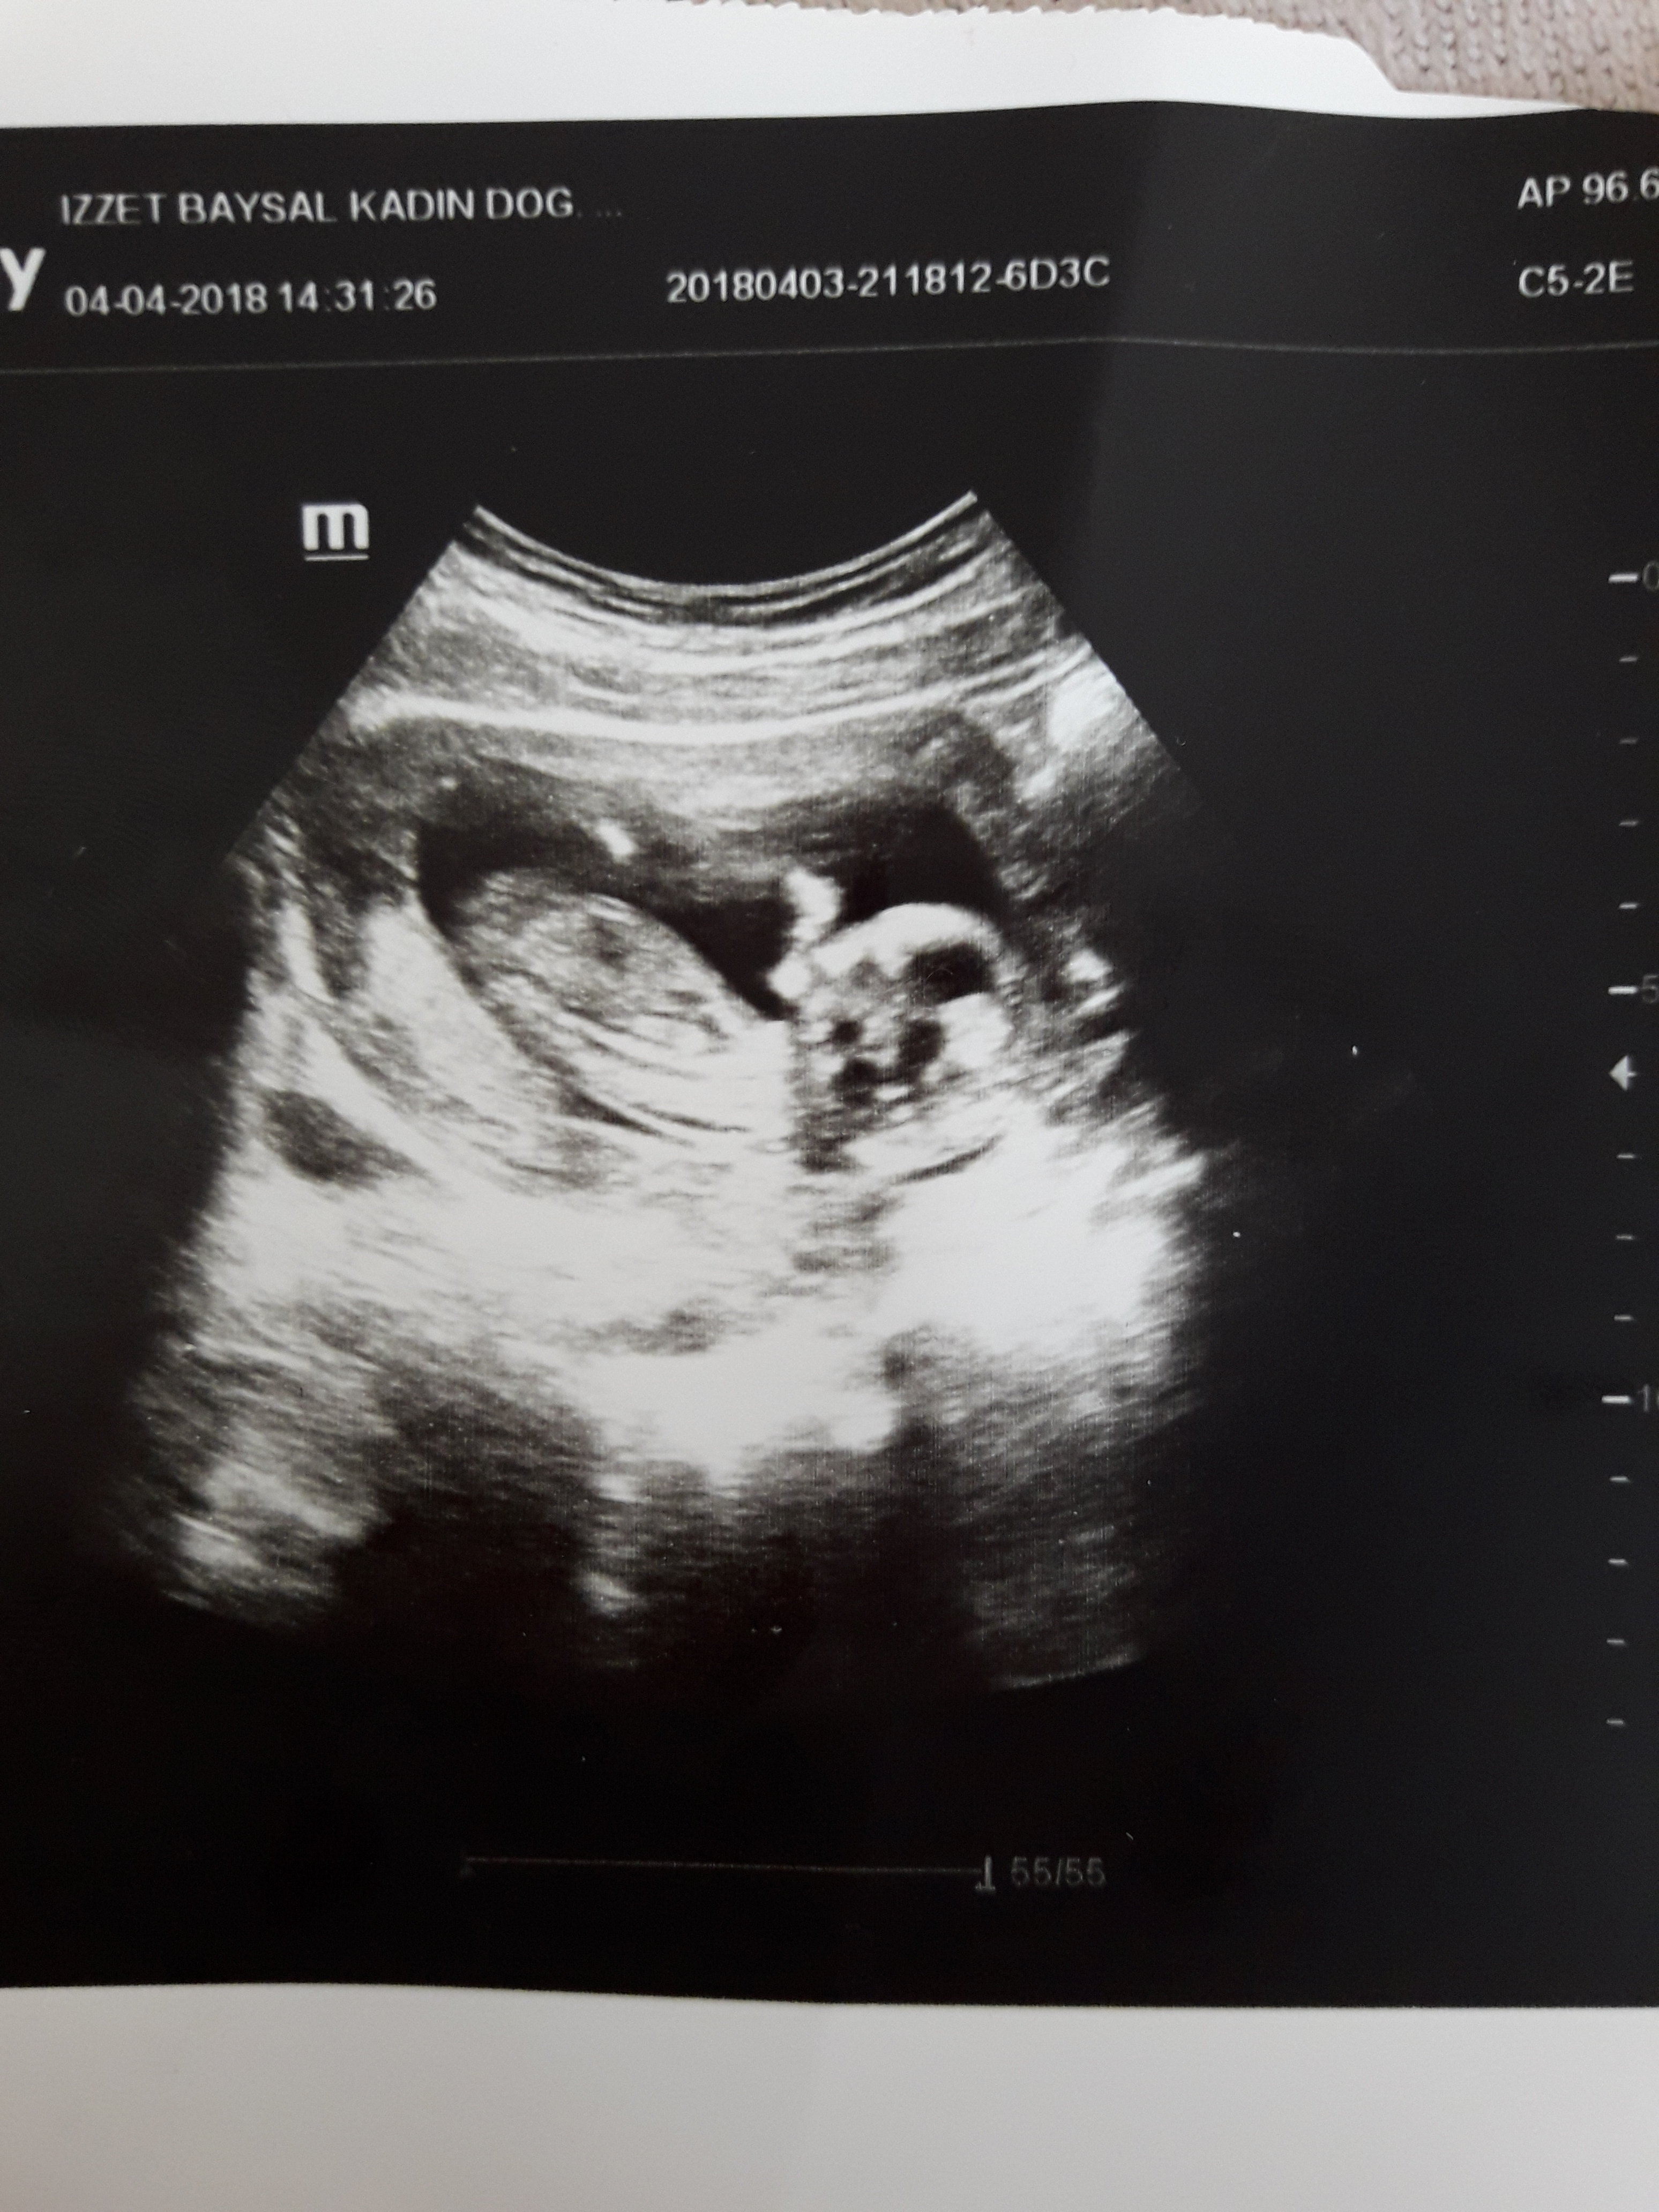

Resim pek net değil emin olmamakla birlikte bebeğinizin cinsiyetinin erkek olduğu kanaatindeyim. Bebeğinizin cinsiyetini 17-19 - 20. haftalarda net olarak öğrenebilirsiniz. Sağlıklı gebelik geçirmeniz dileği ile.

Gercekten mi. Birazda olsa yuregme su serptniz. Erkek cocugum olmasini cok istiyorum. Bu usg ye bakinca nub teorisinden dolayi kiza benzettim biraz icim burkulmustu. Peki nasil anladiniz erkek olduğunu cok merak ediyorum